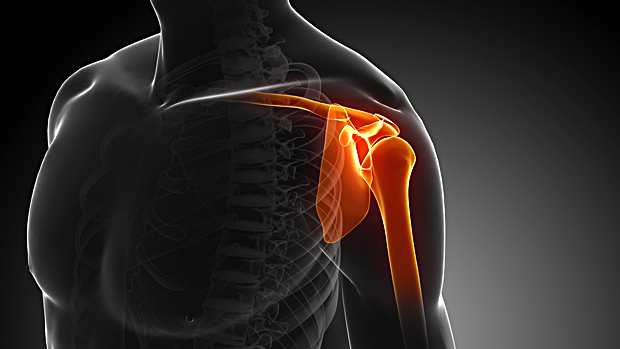

Γράφει ο Αδάμ Αθανάσιος, Χειρουργός Ορθοπαιδικός στη Θεσσαλονίκη Συνεργάτης Euromedica-Γενικής Κλινικής Θεσσαλονίκης Τηλ: 6974108266 Τι είναι η αρθροσκόπηση ώμου; Η αρθροσκόπηση του ώμου είναι μία ελάχιστα επεμβατική μέθοδος (MIS-Minimal Read More…

Αρθροσκόπηση ώμου Γράφει ο Αδάμ Αθανάσιος, MD, FICS Χειρουργός Ορθοπεδικός Συνεργάτης της Euromedica, Γενικής Κλινικής Θεσσαλονίκης Τηλ. 6974108266 Ο ώμος είναι άρθρωση η οποία κινείται σε πολλές κατευθύνσεις και σε Read More…